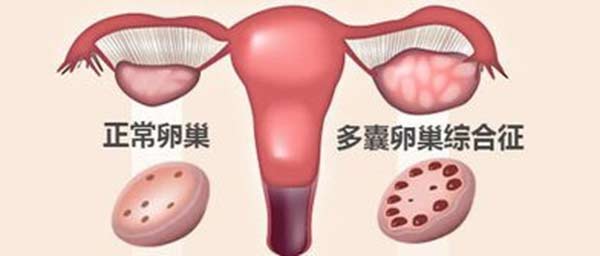

多囊卵巢综合症是生育年龄妇女常见的一种复杂的内分泌及代谢异常所致的疾病,以慢性无排卵(排卵功能紊乱或丧失)和高雄激素血症(妇女体内男性激素产生过剩)为特征,主要临床表现为月经周期不规律、不孕、多毛和/或痤疮,是最常见的女性内分泌疾病。 康安途专 ...

朋友曾对我说,要是真决定了做试管,那就去泰国做,成功率高不说,服务也比国内强多了。在她的建议下,身患多囊的我,通过泰国的试管婴儿技术成功怀上宝宝,如今给大家分享下我的成功经验。 ...